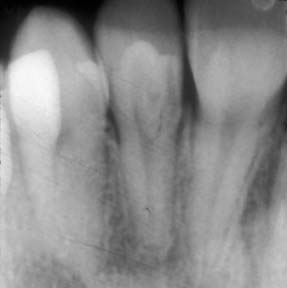

Sometimes, when a cavity is treated; the dentist may find that the cavity is larger or occupies more of the tooth than what we thought. Sometimes the adjacent tooth can also have a cavity that may not have shown up on the x-ray but is visible when the opposing tooth surface has been opened up.

We follow the American Academy of Dentistry and American Academy of Pediatric Dentistry guidelines for taking dental X-Rays. Dental x-rays will be taken as needed during their routine cleaning appointments to check for cavities in between their teeth, survey erupting teeth, diagnose bone disease, evaluate the results of an injury, or plan orthodontic treatment. We will always minimize your child’s radiation exposure by prescribing X-Rays on an individual basis which depends on your child’s individual risk factors for oral disease. Your child will also wear a lead body apron during the process. If you have any concerns about X-Rays for your child, please discuss them with our staff.

A cavity that involves the nerve (pulp) of the tooth may cause a child to experience intense pain. Although the pain may subside for a period of time using ibuprofen or antibiotics, it will return unless the tooth is properly treated. When the nerve of the tooth is infected, it must be treated to restore the child to good dental health.

A pediatric root canal procedure is referred to as a “pulpotomy.” The purpose of root canal treatment is to maintain the vitality of the affected tooth so that the tooth will not be lost early. Early loss of posterior (back) primary teeth may cause future problems with the eruption of permanent teeth. Therefore, it is best to avoid early loss of primary molars by properly treating the nerve of infected teeth with a pulpotomy. Dental caries (cavities) and traumatic injury are the main reasons for a tooth to require pulp therapy. The pulpotomy root canal procedure removes the infected pulp tissue within the crown of the tooth. A medication is placed to calm the nerve of the tooth and prevent bacterial growth. The pulpotomy is followed with a final restoration of a stainless-steel crown.